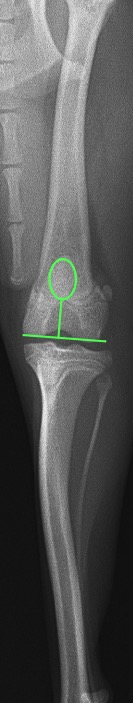

次の2枚の写真はパテラアルタのある今回の子と正常の子の膝関節と膝蓋骨の位置を示したものです。

脱臼時の膝関節

パテラアルタの膝関節

正常膝関節